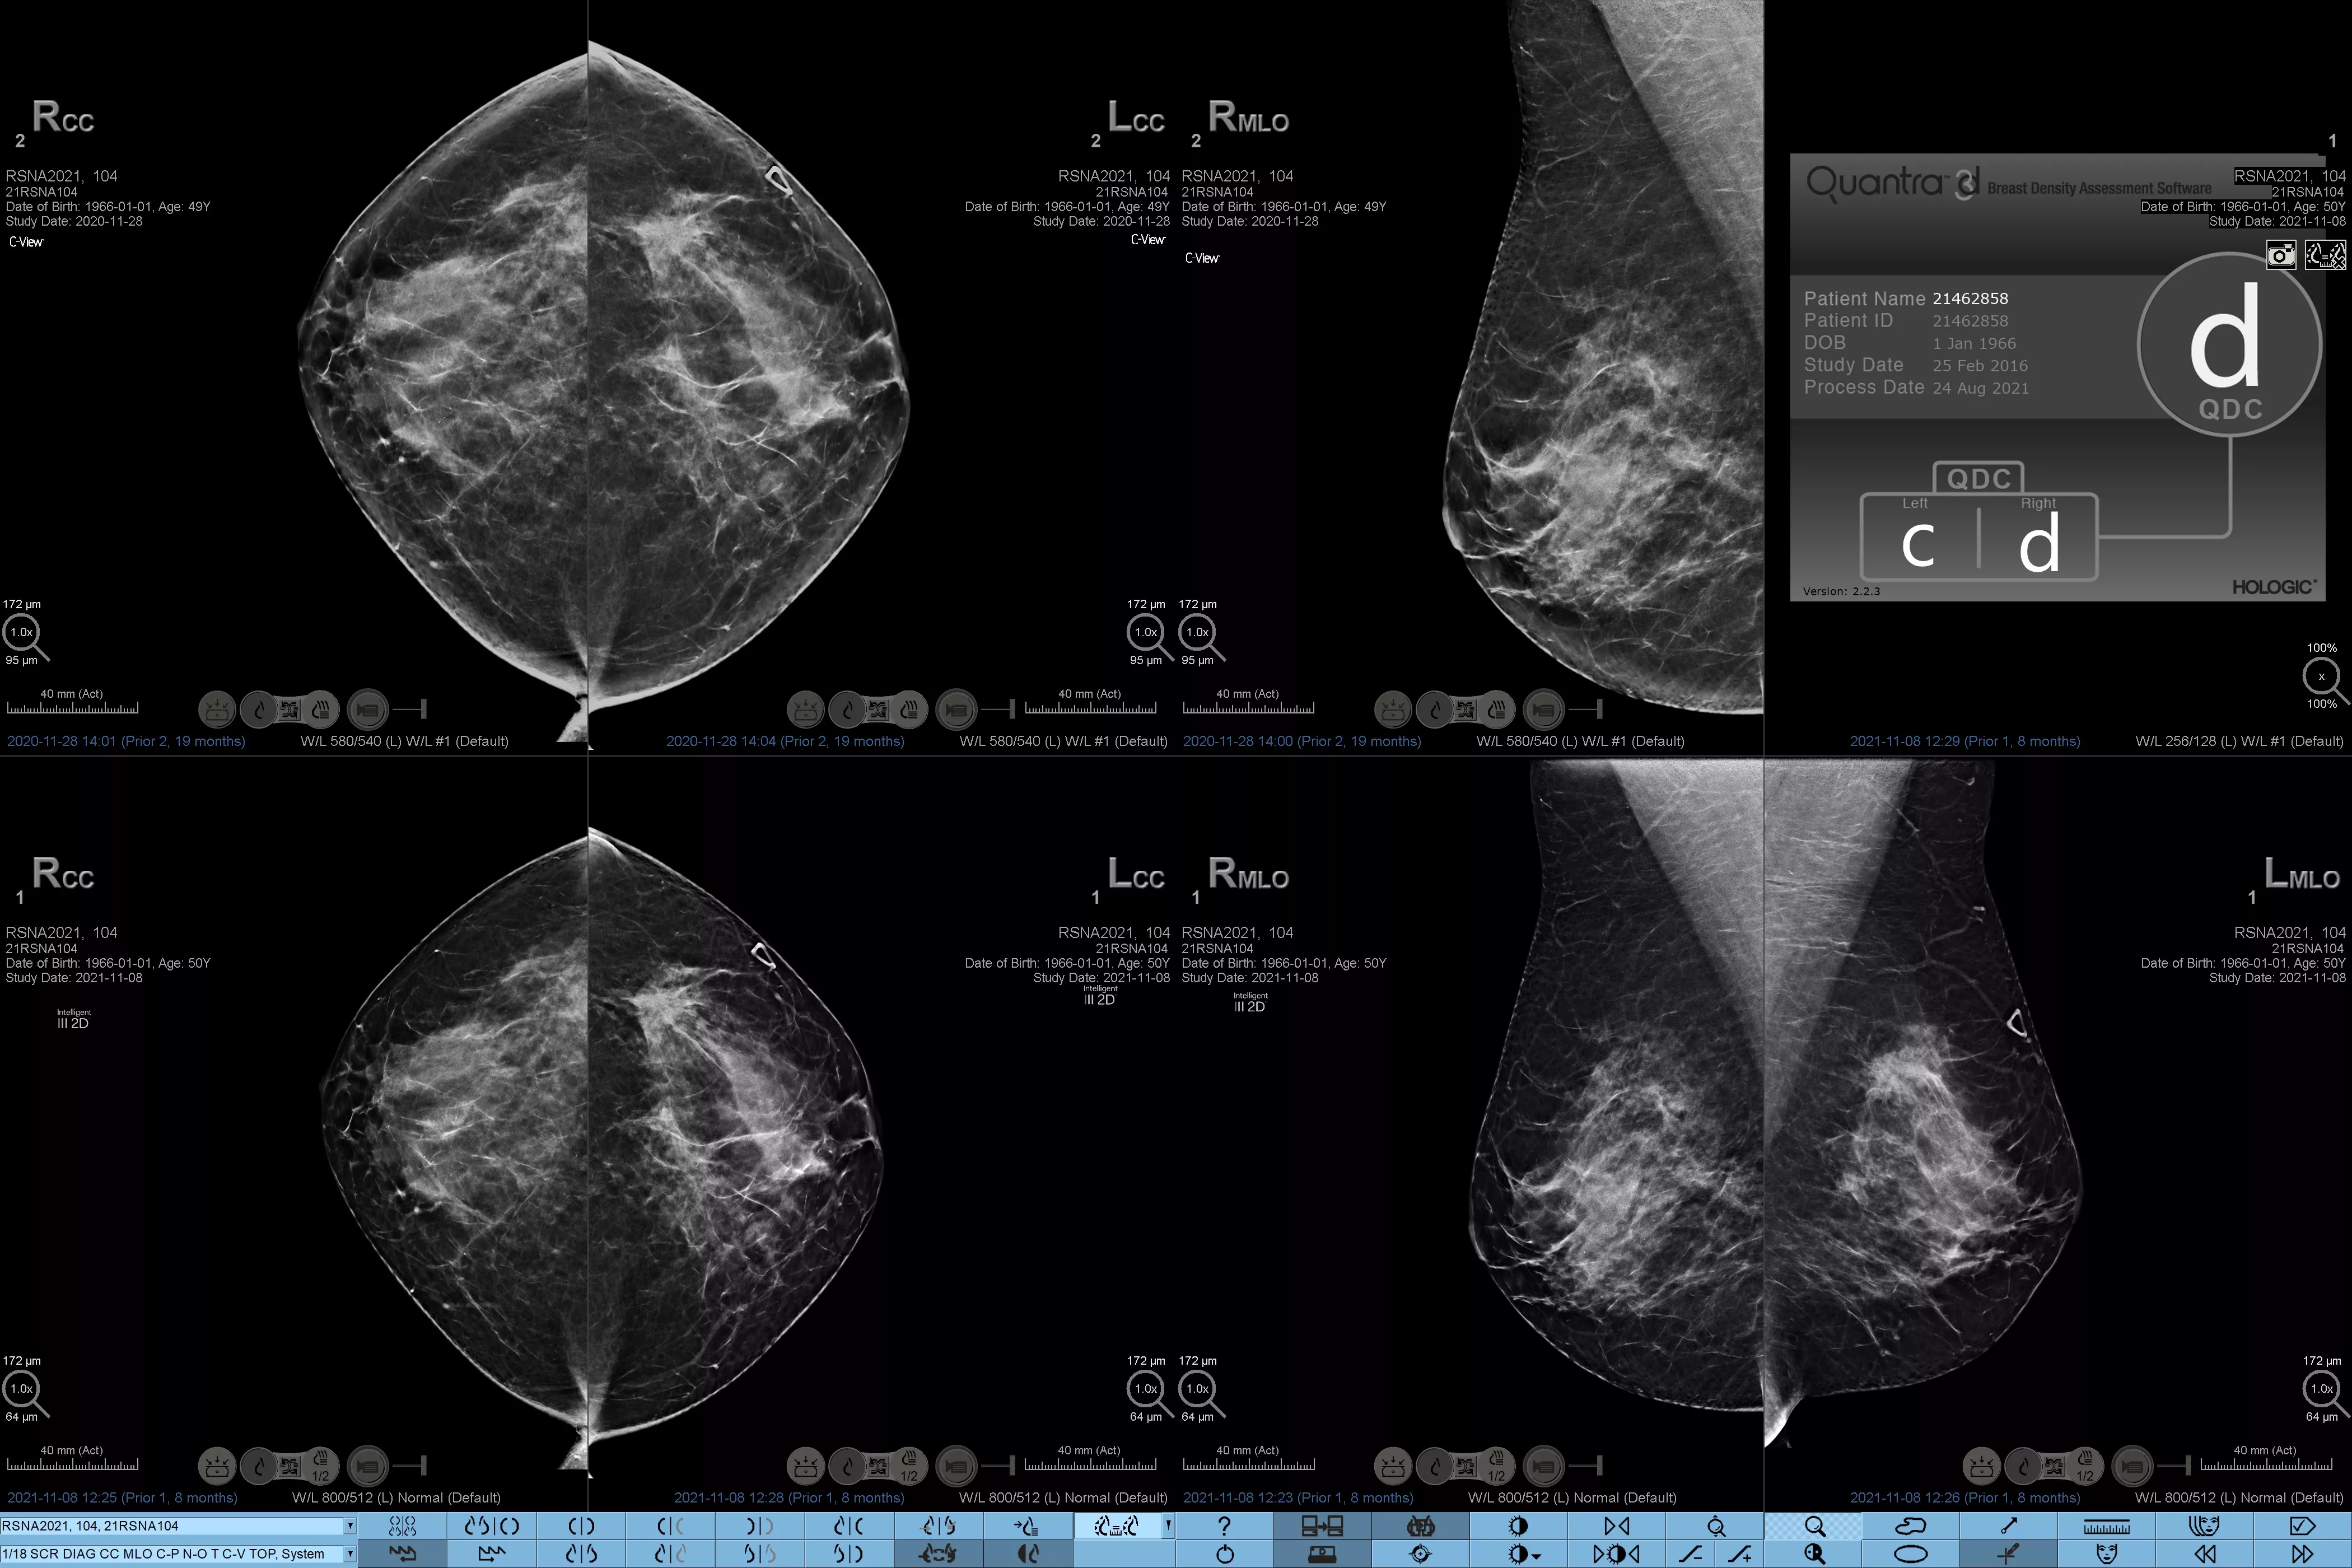

Eine höhere Brustdichte geht bekanntlich mit einem höheren Brustkrebsrisiko einher.1 Eine präzise, objektive Analyse ist daher entscheidend. Die durch maschinelles Lernen unterstützte Software der Quantra Technologie analysiert sowohl 2D™- als auch Tomosynthese-Bilder in Bezug auf Verteilung und Textur des Parenchymgewebes. Sie teilt die Brüste entsprechend der Leitlinie der 5. Auflage des BI-RADS Atlas des American College of Radiology (ACR) nach ihrer Zusammensetzung in vier Brustdichte-Kategorien ein.2

Objektiver Machine-Learning-Algorithmus, der die Brustdichte-Kategorie auf Basis der Analyse von Textur und Muster des Brustgewebes zuordnet.

Der objektive Algorithmus der Quantra-Software analysiert sowohl 2D- als auch Tomosynthese-Bilder und unterstützt Sie bei Ihrer Analyse durch:

• Unabhängigkeit von subjektiver visueller Beurteilung für eine konsistentere und zuverlässigere Einstufung.*

*Die Scores basieren auf den ACR BI-RADS-Kategorien nach den revidierten Leitlinien der 5. Auflage des vom American College of Radiology (ACR) herausgegebenen BI-RADS-Atlas. Dadurch werden Struktur und Textur im Vergleich zum Volumen bei der Dichtebestimmung berücksichtigt.